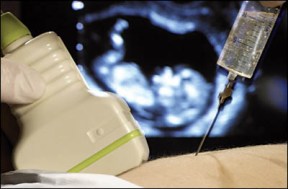

Амниоцентеза претставува дијагностичка метода која дава важни информации за состојбата на плодот и можните генетски пореметувања. Процедурата опфаќа боцкање на стомачниот ѕид на бремената жена и земање примерок од околуплодовата вода. Заради поголема прецизност и безбедно боцкање во текот на интервенцијата движењето на иглата се следи со ултразвук (ехо).

Како и другите инвазивни методи и амниоцентезата со себе носи определен минимален ризик. Кај околу 1% од изведените процедури постои ризик од спонтан абортус по направена амниоцентеза. Употребата на ултразвукот во денешно време значително го намалува ризикот од крварење, а постои и минимален ризик од инфекција при боцкањето.